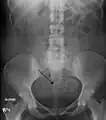

A very large (9 cm) fibroid of the uterus which is causing pelvic congestion syndrome as seen on CT

Two calcified fibroids (in the uterus)